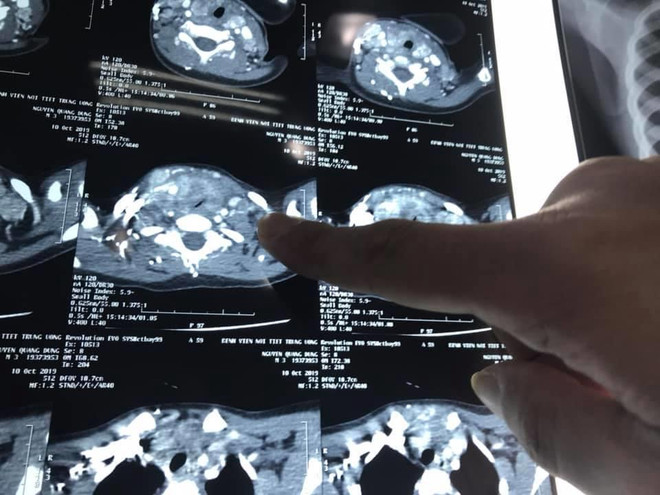

Bé trai 3 tuổi mắc ung thư tuyến giáp, di căn nhiều hạch ảnh 2Phim chụp của bệnh nhân mắc ung thư tuyến giáp nhỏ tuổi nhất. (Ảnh: PV/Vietnam+)

Tại đây, sau khi thực hiện các chỉ định cận lâm sàng, bé D. được chẩn đoán ung thư tuyến giáp với mức độ di căn nhiều hạch cổ 2 bên. Khối u đã phát triển lớn chèn ép khí quản gây khó thở.